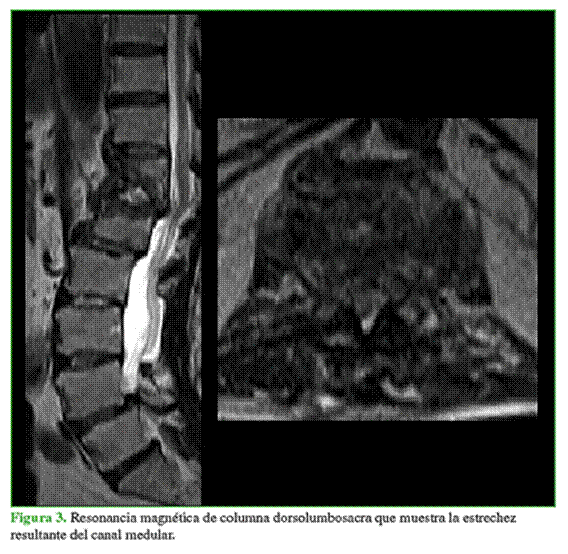

En la resonancia magnética, se visualizó el estrechamiento del canal espinal en T12-L1, con hiperintensidad en la secuencia T2 del disco a dicho nivel, asociado con la destrucción de ambos cuerpos vertebrales (Figura 3). Se realizó, además, un centellograma óseo que mostró hipercaptación leve en T12-L1. Los parámetros bioquímicos indicaban que no había infección activa.